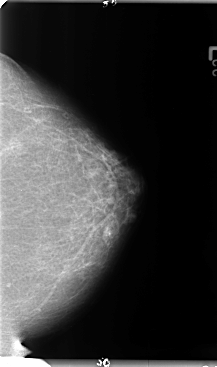

B_3124_1.LEFT_CC

LEFT_CC LINES 4768 PIXELS_PER_LINE 2816 BITS_PER_PIXEL 12 RESOLUTION 50 NON_OVERLAY